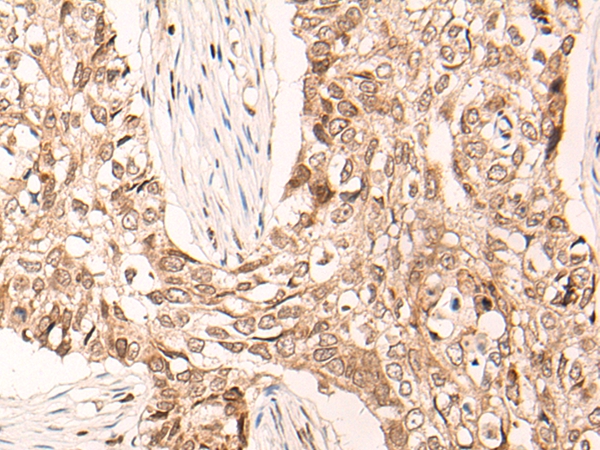

The image on the left is immunohistochemistry of paraffin-embedded Human lung cancer tissue using 46603(MAFB Antibody) at dilution 1/30, on the right is treated with synthetic peptide. (Original magnification: x200)